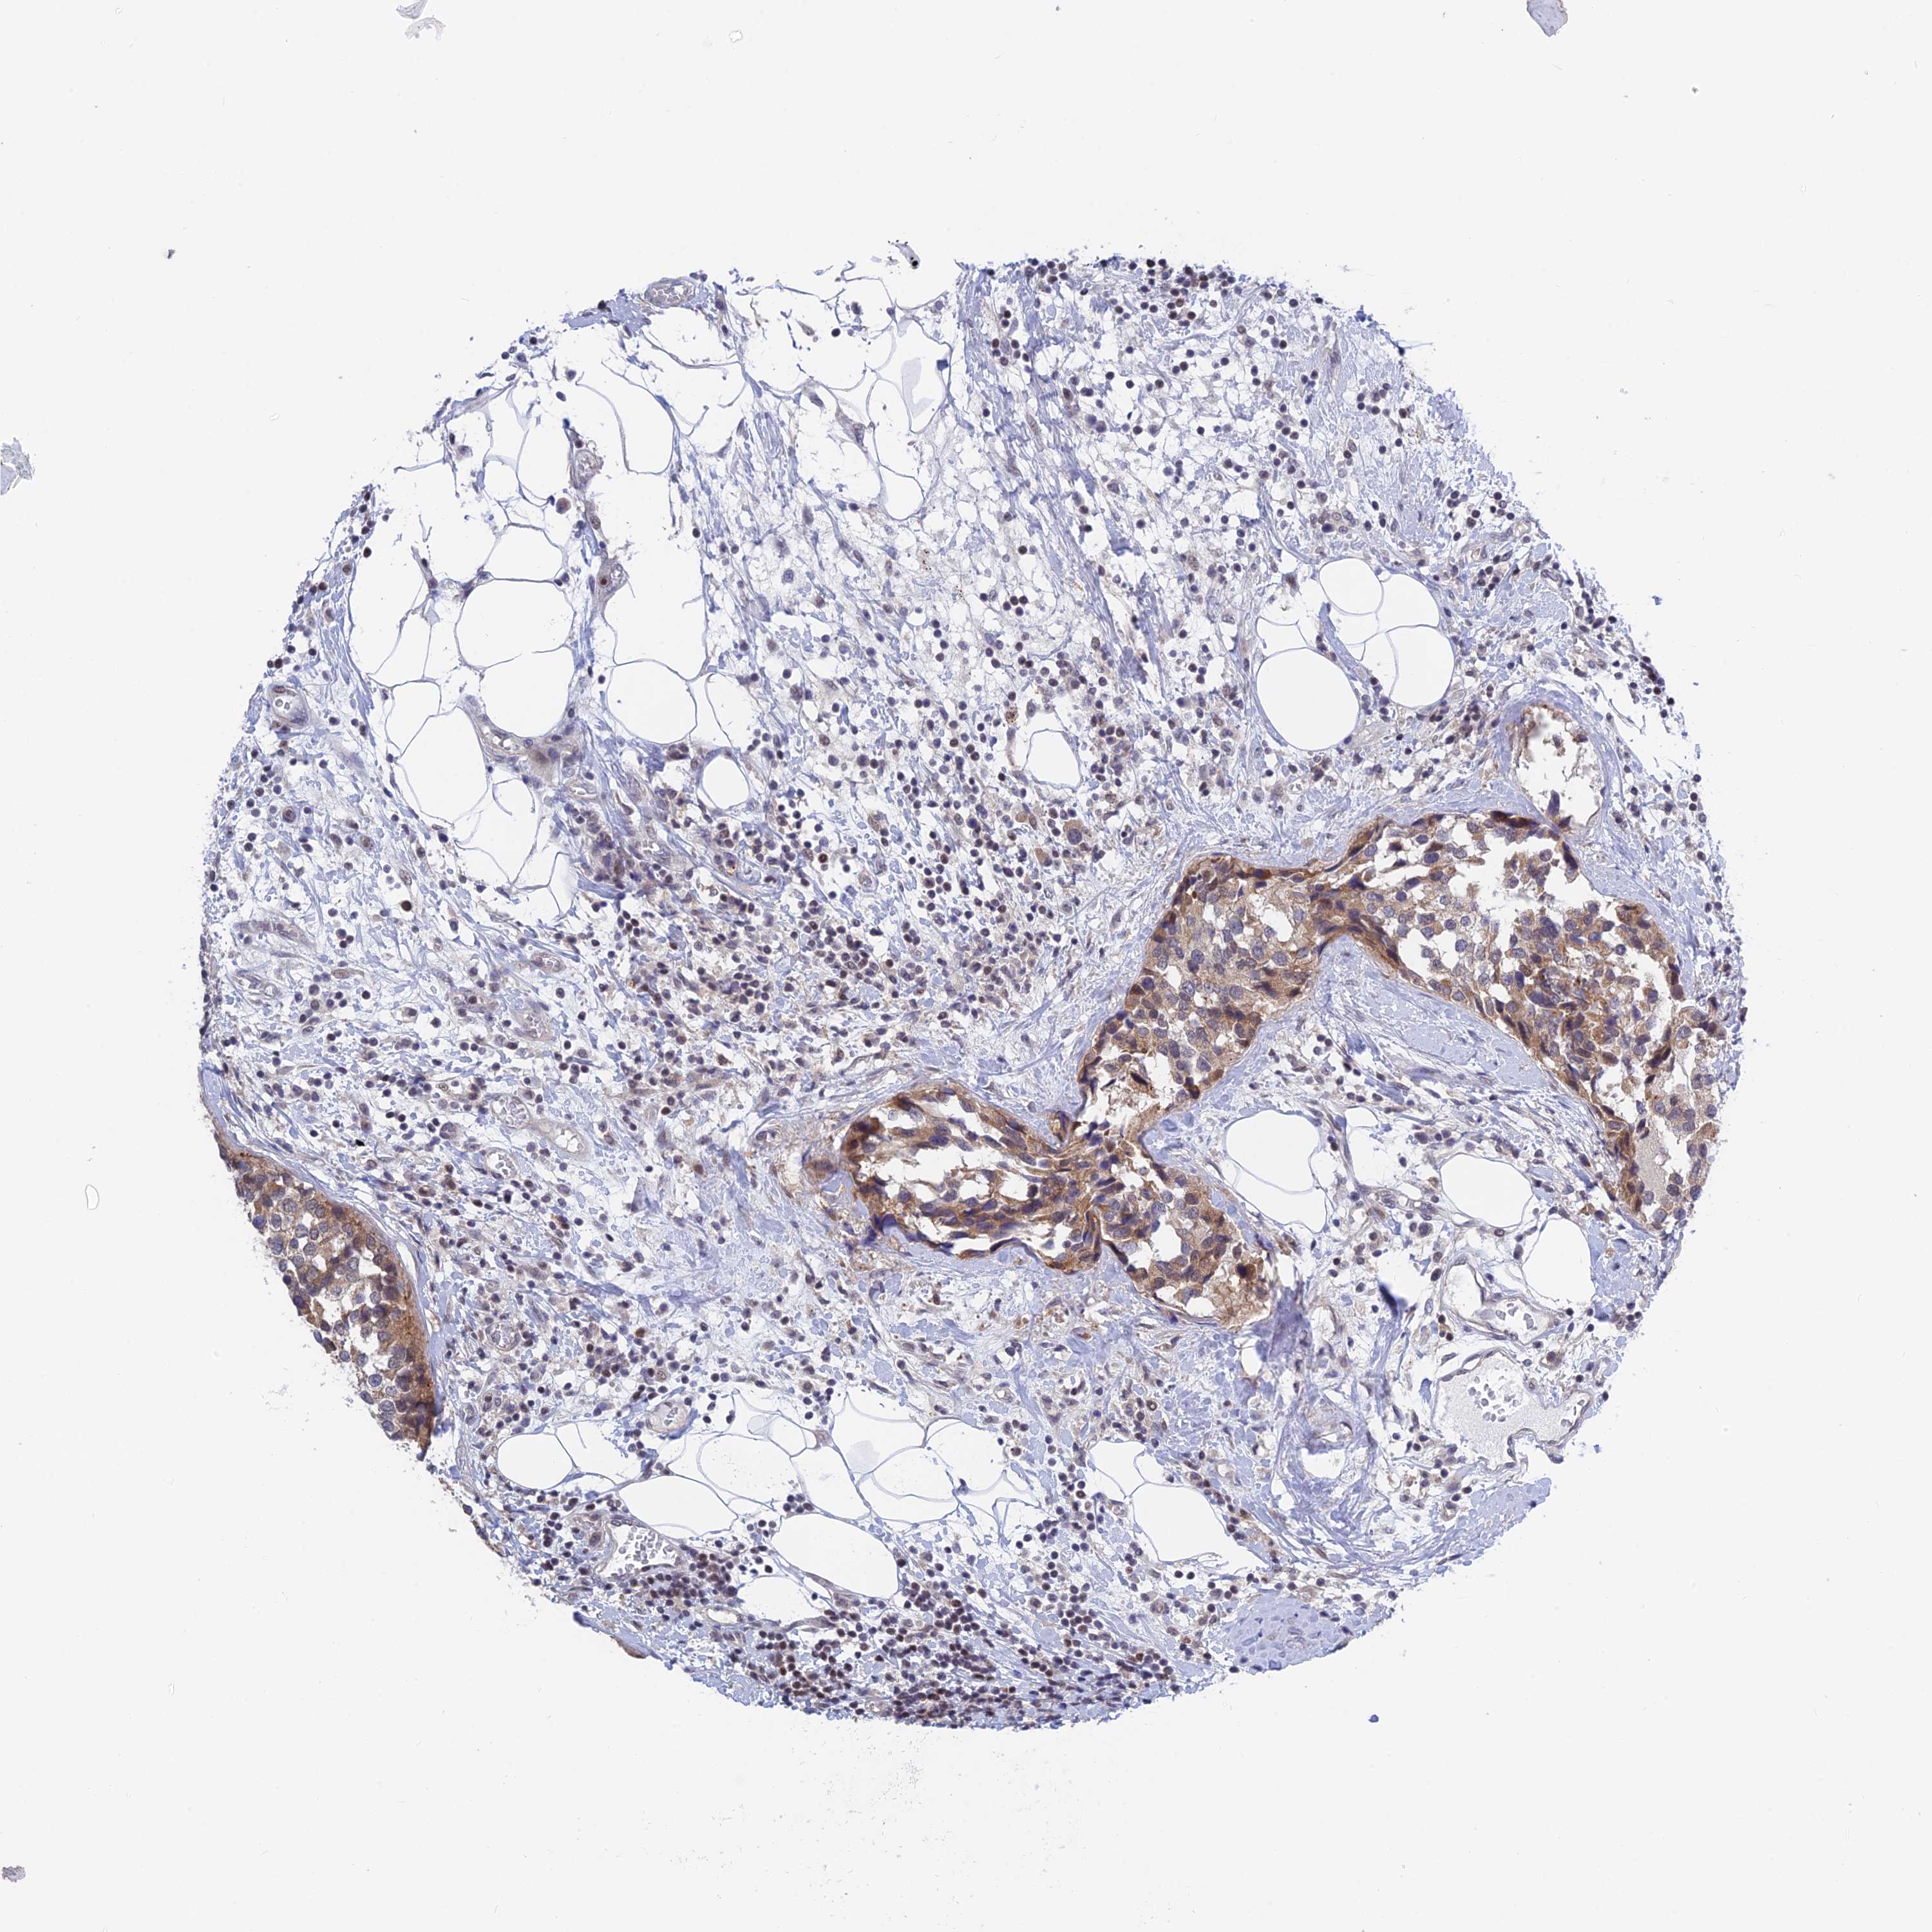

CANCER BREAST CANCER Show tissue menu

BRCA TCGA BRCA VALIDATION PROTEIN EXPRESSION